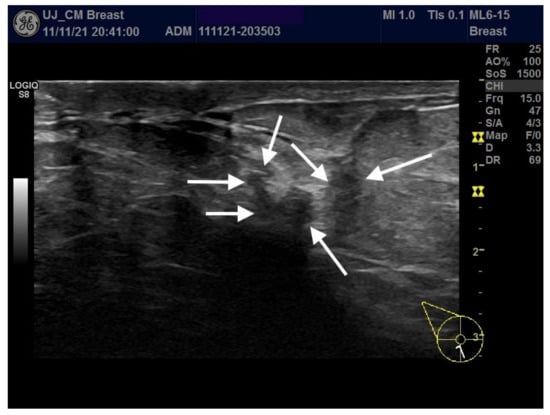

5. Clinical Picture, Diagnostic Criteria

6. Imaging Findings